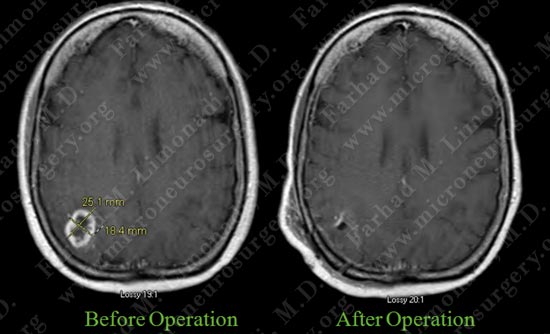

Post-op Imaging

Post op MRI shows complete resection of the tumor with no injury to surrounding neuro-vascular structures.